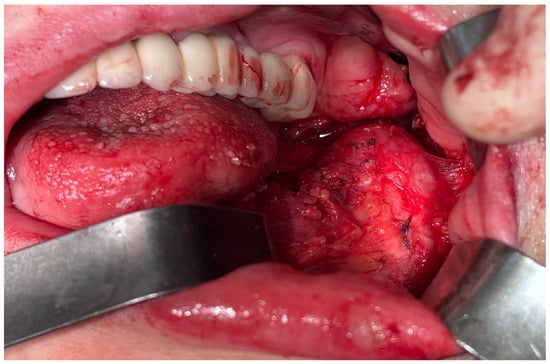

2.4. Second Surgical Intervention